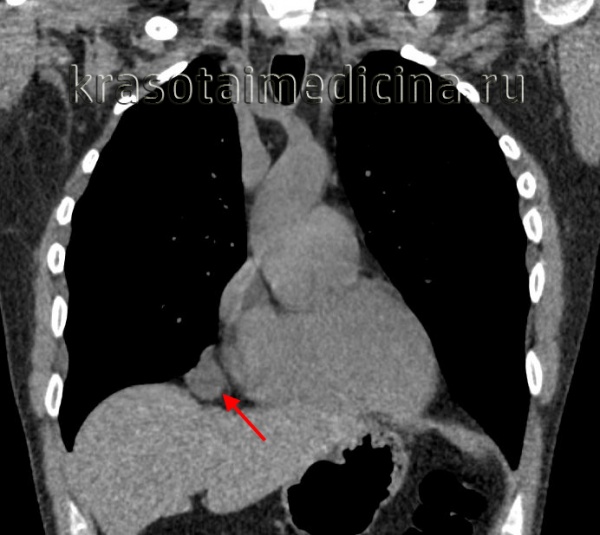

Высокоинформативным способом диагностики тератом является КТ пораженной области. Методика позволяет определить форму, размер и строение опухоли, а также оценить ее взаимосвязь с другими анатомическими структурами. При подозрении на наличие метастазов назначают КТ, МРТ, рентгенографию грудной клетки, сцинтиграфию и другие исследования. В качестве уточняющего метода применяют анализ крови на хорионический гонадотропин и альфа-фетопротеин. Окончательный диагноз выставляют с учетом результатов пункционной биопсии и последующего микроскопического исследования материала.

- Рентгенологические исследования. Полипозиционная рентгеноскопия и рентгенография грудной клетки, рентгенография пищевода и сердца, пневмомедиастинография позволяют определить локализацию, форму и размеры кисты, ее связь с соседними органами, изменение положения при дыхательных движениях.

- Томографическая диагностика. Для более детальной оценки структуры, толщины стенок кисты, характера содержимого и взаимоотношения с соседними анатомическими образованиями, производится КТ и МРТ средостения.